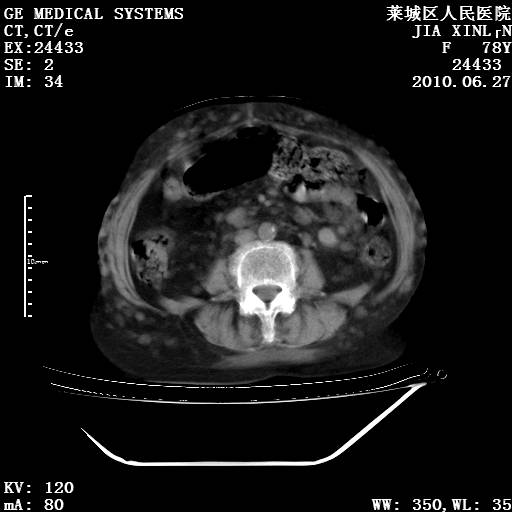

以下是引用胡宇在2010-7-2 19:11:00的发言:[br]神经纤维瘤的特点为:肿块呈多发性、数目不定,少的几个,多的可成百上千难以计数。小的如米粒,大的似拳头,甚至可达十数公斤以上。可松弛地悬挂于皮表,皱褶及松弛可致畸形明显。神经纤维瘤沿神经干的走向生长时呈念珠状,或蚯蚓块状形结节。此外神经纤维瘤皮肤可出现咖啡斑,大小不一,形如雀斑小点状,或大片状,分布与神经纤维瘤肿块的分布无关。肿瘤数目不多的患者,皮肤色素咖啡斑状沉着是纤维神经瘤的重要诊断之一。 本病多发于躯干,有时出现于四肢及面部,患者常合并许多疾病应予重视加以区别。 [br] [br] [br] [br]lyb999说 [br]